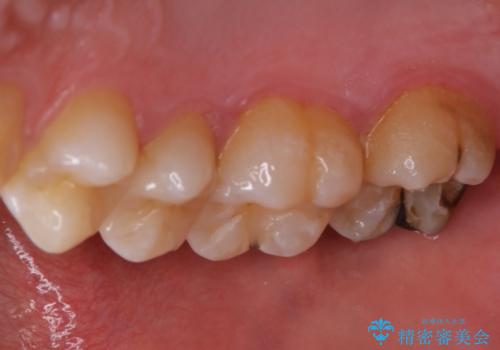

広範囲にわたる虫歯をセラミックで治療

- 他県より引っ越しをされたため、途中になってしまっている虫歯治療の続きをしてほしいと来院された患者様です。

痛み等の自覚症状はありませんでしたが、広範囲にわたる虫歯を認めたため、セラミッククラウンによる治療を行いました。

今回のケースでは、一番奥の歯の後ろ側に向かって虫歯が進行していました。一番奥の歯は元々の歯の高さが低いことが多く、被せ物が割れるリスクが増加したり、被せ物が外れやすくなる場合があります。歯牙切削量の少ないゴールドアンレーもご提案しましたが、セラミックをご希望されたため、今回はクラウンによる治療を行いました。